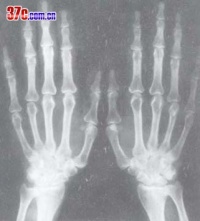

2.胸部、受累关节X线片,脑CT磁共振检查 。必要时作肾脏及腹部B超检查及上消化道内镜检查。